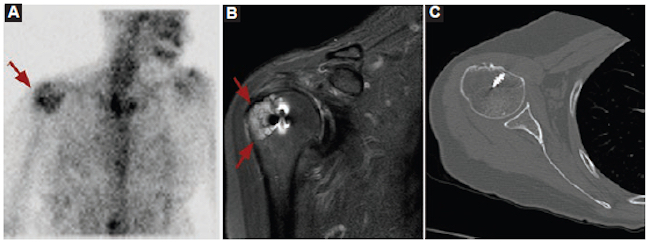

Varón de 50 años con antecedentes de diabetes que se internó por neumonía y presentó también una tumoración en la pierna derecha, de crecimiento lento, sin recordar ningún episodio traumático. La RM informó lesión de aspecto tumoral, considerando el sarcoma de partes blandas como principal diagnóstico diferencial, y se sugirió su biopsia. El resultado de la biopsia guiada por ecografía informó material fibrinoide con escasa cantidad de células. Ante la imposibilidad de descartar una neoplasia, se realizó resección quirúrgica con márgenes oncológicos (Fig. 3).

El resultado de anatomía patológica evidenció un hematoma organizado. El paciente evolucionó clínicamente estable y se le otorgó el alta hospitalaria.